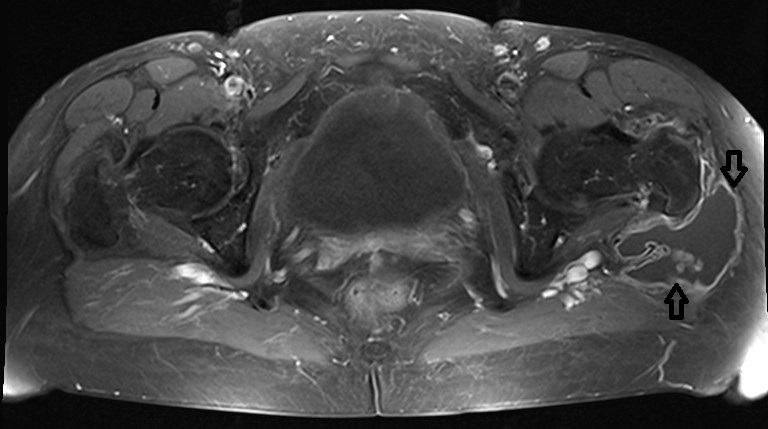

This is the first report on a localized pigmented villo-nodular synovitis (PVNS or TSGCT) occurring in the trochanteric bursa. Bursal involvement in PVNS is extremely rare. Most often PVNS occurs either as a localized or diffuse lesion in a major synovial joint, such as the knee, ankle joint or hip joint. In principle, all synovial structures can be involved. The case reported here is remarkable regarding the long period between the occurrence of the first symptoms and the final diagnosis as well as the age of the female patient (75 yrs). Therapeutically a complete resection was performed in order to avoid recurrence. More then three years later the patient did well and there has been no evidence of recurrence yet.